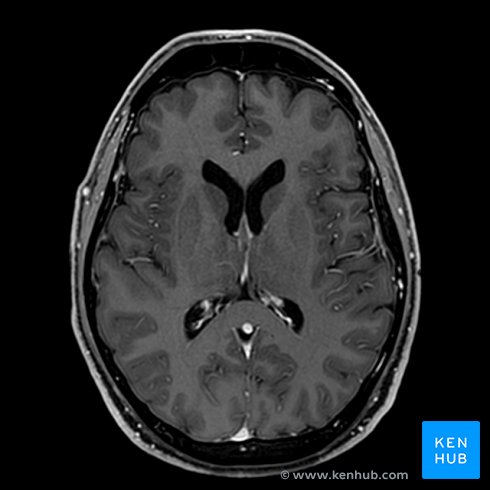

However, a lot of medical schools throughout the world have either reduced or completely eliminated this method of teaching in the 21st century. Nowadays, anatomy is taught via methods that would have gobsmacked the anatomy heavyweights, such as prosections (dissections performed by an experienced anatomist and later used for teaching), 3D models, imagistics, virtual tables (Anatomage), and virtual reality. In addition, many schools have dramatically reduced the number of anatomy hours or use a problem-based learning curriculum in which anatomy is learned on the go. Is this is a good thing or a bad thing? Actually, the answer is not black or white, but rather an ugly grey with many factors playing a part.